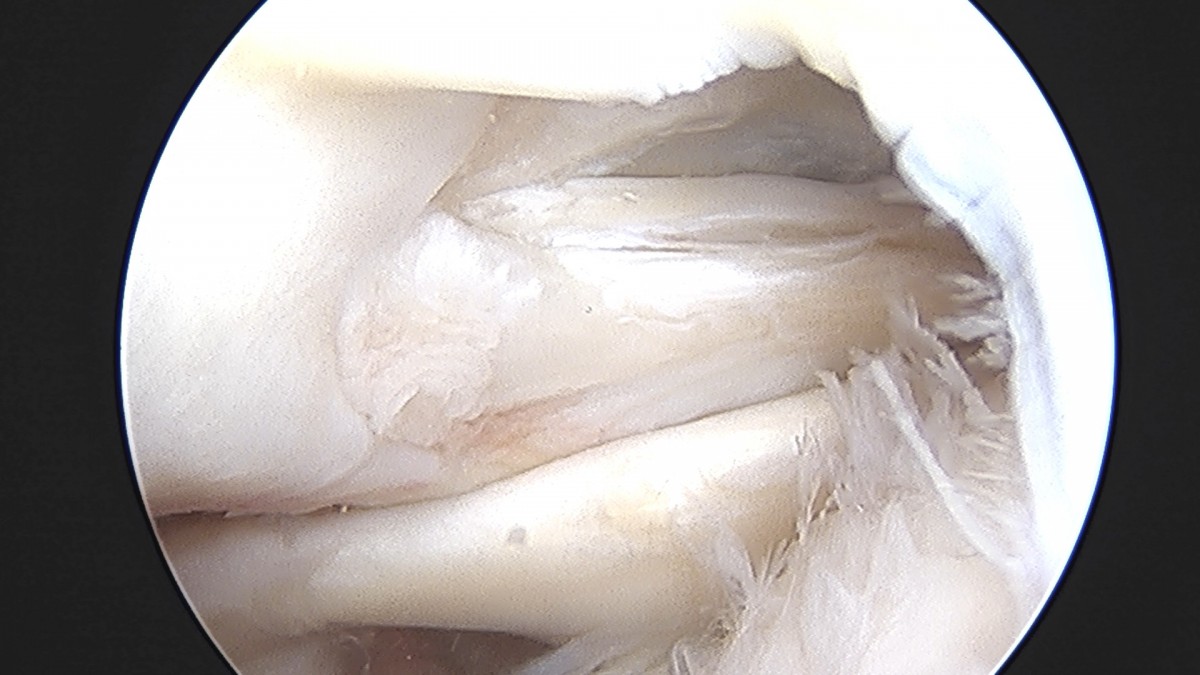

정지영원장님 어깨 회전근개 봉합술 김영O 환자

dae765e4d9ac96aee867c9d6292d8784_1758009060_4312.jpg